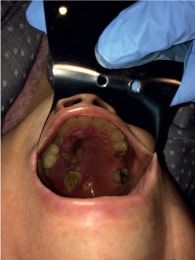

Paciente femenino de 61 años de edad que presenta diabetes mellitus no controlada de 15 años de evolución e hipertensión y con antecedentes heredo familiares de las mismas enfermedades. Se presenta al servicio de patología de la universidad; a la exploración intrabucal presenta dos úlceras en paladar, la mayor de 1.5 x 1.1 cm y la menor de 1.2 x 1.3 cm con presencia de fondo necrótico y a la palpación se percibe presuntamente la lisis del paladar en ambas úlceras. Refiere sintomatología de 1 semana de evolución con cefalea intensa que no cede a los analgésicos. Identificando aliento cetónico y refiriendo no seguir dieta adecuada.